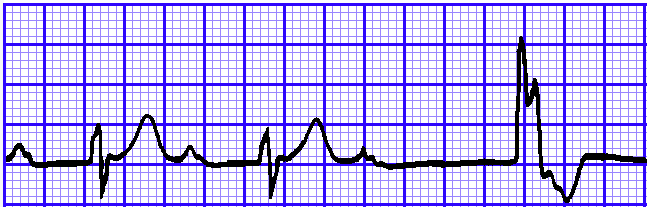

4、M波

M波是指QRS波群程序“M”形态,主要见于右束支传导阻滞,V1和V2导联上出现“M”形表示右束支传导阻滞,这里的“M”形是指出现两个R波,QRS波群呈现rsR’、RSR’或rR’形态。而与V1、V2导联对应的V5、V6导联则会出现与之相对的类似导致的宽S波,具体见下图。

而判断束支传导阻滞是否完全,主要看QRS波群的时限,QRS波群>0.12s,就是完全性的,反之就是非完全性的。具体如下图。

图11